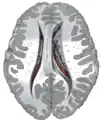

Transverse cut of brain (horizontal section), basal ganglia is blue  | |